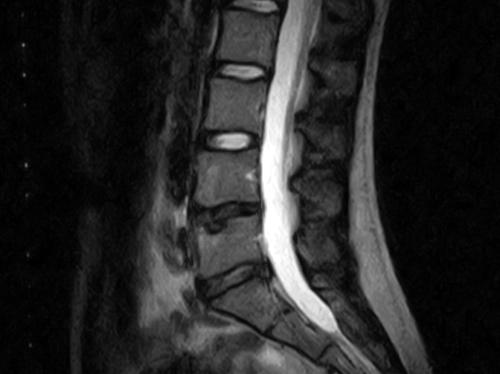

LDH=腰椎椎間板ヘルニア:髄核/線維輪が後方(主に後外側)へ膨隆・脱出し、神経根や馬尾を圧迫して症状が出る状態。

画像解釈の落とし穴:無症候の膨隆・ヘルニア所見は珍しくない。画像と神経学的所見の一致が診療の軸。

無痛の膨隆/線維輪断裂/脊髄形態変化は40代で相当数見られる。症状と一致しなければ原因と断定しない。

座位や前屈で増悪。MRIで把握しやすい。